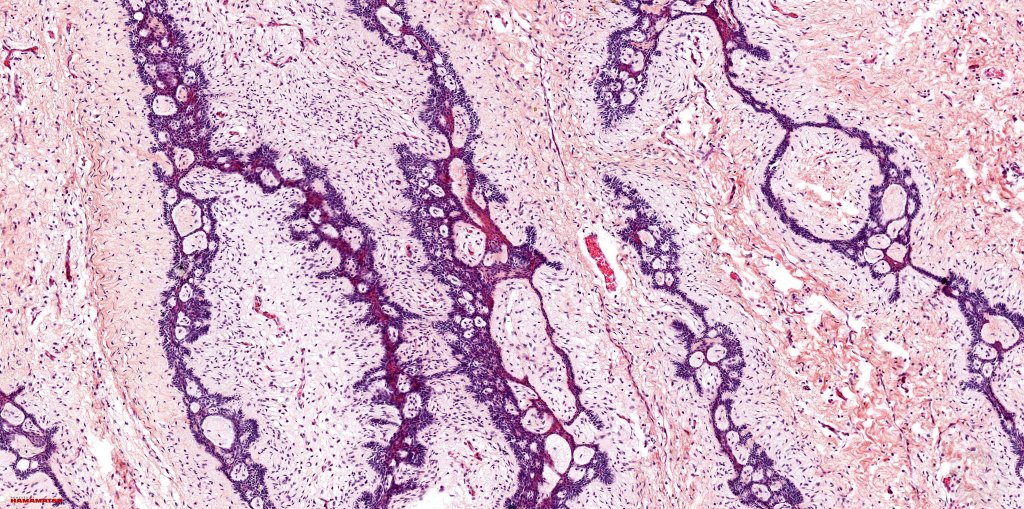

Histological features

•Anastomosing basaloid, narrow epithelial strands associated with a prominent fibrous (sometimes myxoid) stroma

•Peripheral palisade

•Hair germs sometimes present

•Occasional cysts